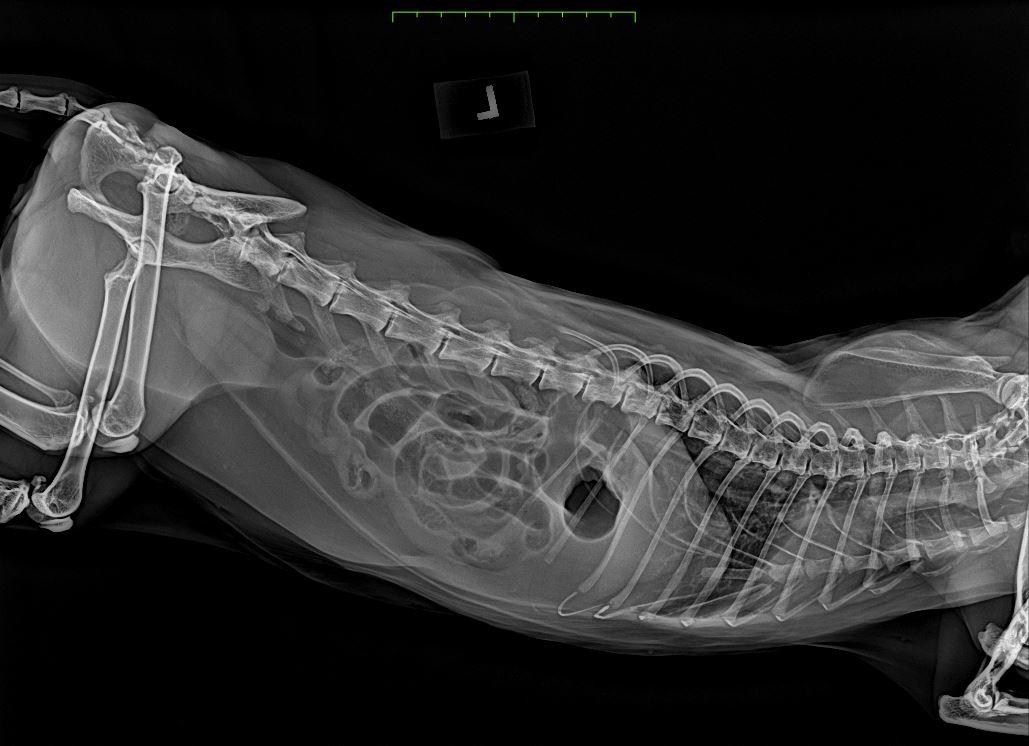

醫生聽了我說明的狀況之後決定要先照 X 光,看是否有異物卡在腸道。

醫生說腸道塞滿空氣,有地方疑似堵塞(但我看不懂)

X 光發現疑似異物的東西,所以接著運用超音波做更詳細地確認。